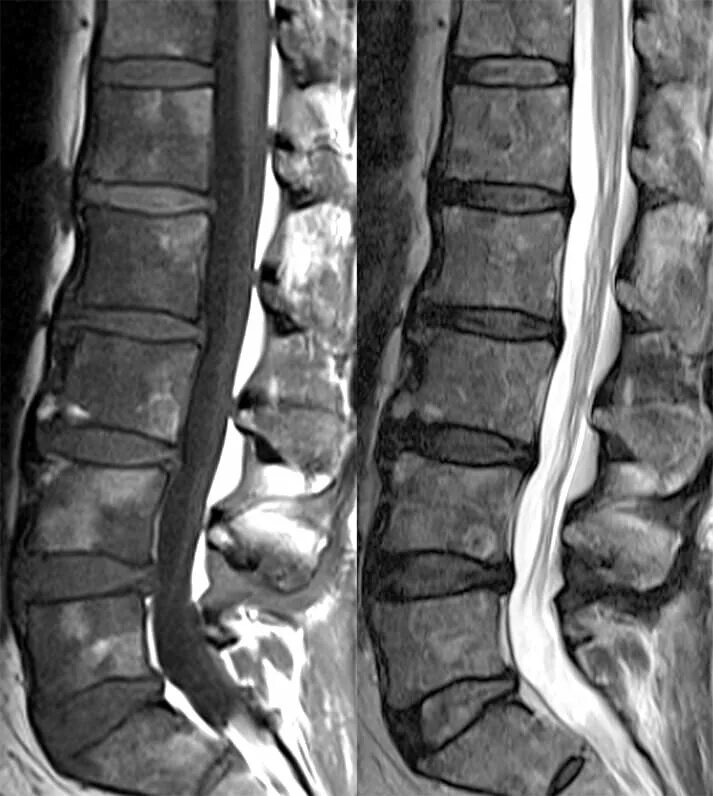

Как выглядят метастазы на мрт